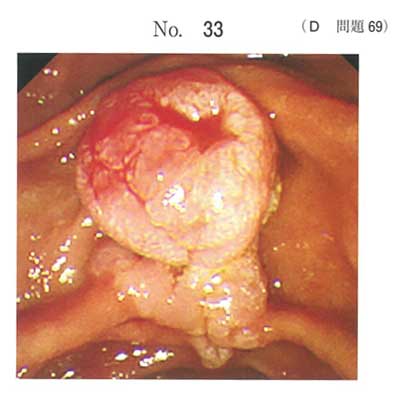

| タイトル:113D-69 | コメント数:5 | 割問 |

血性であり汚いので悪性を疑いました

A、E

2: 消化器内科医

a,e

肝障害や腹部症状が出現しておりドレナージは必要ですが、胆管炎を発症しているわけではないため生検、MRIなどで精査しつつ、待機的に行うのが良い。

また、ドレナージは侵襲等考慮し、最初は内視鏡的にアプローチするのが基本なのでdは☓ですね。

また、肉眼的に十二指腸乳頭部の腫瘍が疑われるため、乳頭切開は禁忌です。大出血する可能性があります……